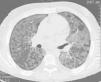

Un varón de 26 años de edad acudió a nuestro centro con disnea. No presentaba fiebre, expectoración ni hemoptisis. Había recibido 7 años antes un trasplante alogénico de células madre hematopoyéticas por anemia resistente, y 3 años antes, un trasplante de riñón por insuficiencia renal crónica relacionada con enfermedad del injerto contra huésped de carácter crónico. En el examen, el paciente presentaba anemia, pero ninguna otra anomalía. Los datos de laboratorio incluían el recuento de leucocitos, que era de 5.230/μl, con un 77% de neutrófilos, un 18% de linfocitos, un de 3% monocitos y un 2% de eosinófilos. La presión arterial de oxígeno era de 58mmHg. Las radiografías de tórax mostraban patrones reticulares bilaterales de mayor opacidad sin afectar a los ángulos costofrénicos. La tomografía computarizada de alta resolución (fig. 1) mostró áreas dispersas de atenuación en vidrio deslustrado, con superposición de engrosamiento septal intra e interlobular (patrón en empedrado). Dado el resultado de los estudios de imagen, se realizó un lavado broncoalveolar mediante fibrobroncoscopia. El líquido del lavado broncoalveolar presentaba a la vista un aspecto lechoso, y microscópicamente contenía macrófagos cargados de lípidos y una gran cantidad de material positivo a la reacción del ácido peryódico de Schiff y resistente a la diastasa. Además, se encontró una concentración elevada de ADN de citomegalovirus en sus células, detectado mediante la técnica de reacción en cadena de la polimerasa en tiempo real. Una vez confirmado el diagnóstico de PAP, se realizó un lavado pulmonar completo. El paciente experimentó una gran mejoría, por lo que se decidió que se llevaría a cabo tratamiento ambulatorio y que se programaría otro lavado pulmonar si estaba indicado. La infección por citomegalovirus se trató con fármacos antivíricos e inmunoglobulina anticitomegalovirus.

En nuestro paciente, la PAP secundaria se desarrolló asociada a inmunodeficiencia y a una reactivación de citomegalovirus. La neumonía intersticial por citomegalovirus es una complicación grave en huéspedes inmunocomprometidos, como los pacientes que han recibido un trasplante. Se ha planteado que la reactivación de citomegalovirus, que afecta a los macrófagos alveolares, podría inducir la PAP6, si bien otros estudios indican que las infecciones oportunistas se solapan con una PAP ya existente2. La infección es una característica común en el curso de la PAP, pero en su modalidad secundaria no está claro si es la causa o el efecto de la infección. La tomografía computarizada de alta resolución muestra un patrón en empedrado. Aunque esta característica radiológica no es patognomónica de la PAP, es sumamente indicativa de ella. Los hallazgos radiográficos típicos de citomegalovirus (nódulos pequeños o mal definidos y consolidaciones densas) no estaban presentes en nuestro paciente, aunque no podemos descartar que la atenuación en vidrio deslustrado pudiera deberse a la infección por citomegalovirus.